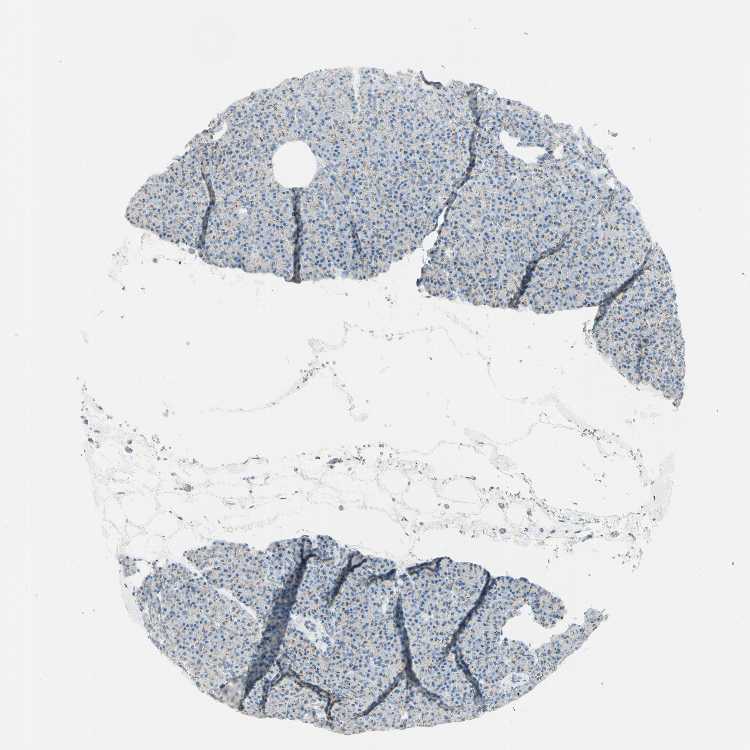

TISSUE PRIMARY DATA PANCREAS Show tissue menu

PANCREAS - Antibody stainingi

Antibody staining in the annotated cell types in the current human tissue is reported as not detected, low, medium, or high, based on conventional immunohistochemistry profiling in selected tissues. This score is based on the combination of the staining intensity and fraction of stained cells.

Each image is clickable and will lead to virtual microscopy that enables deeper exploration of all samples and also displays staining intensity scores, fraction scores and subcellular localization as well as patient and tissue information for each sample.

Antibody HPA010806Antibody HPA010807

Exocrine glandular cells Not detectedMedium

Pancreatic endocrine cells Not detectedLow